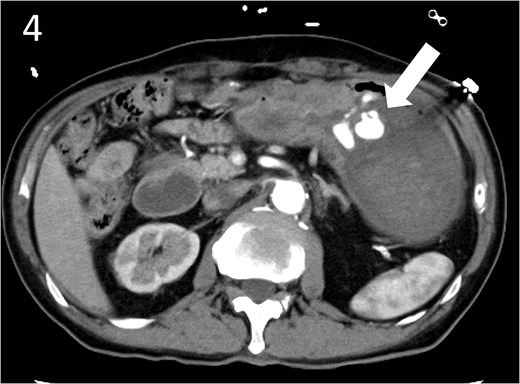

A 78-year-old man was transferred to our hospital because of hypovolemic shock. He had already received 10 units of RBC concentrate. His blood pressure was 97/64 mmHg. The patient’s haemoglobin level was 8.2 g/dL. Contrast-enhanced CT showed active contrast extravasation in the stomach (Fig. 4). Emergency angiography revealed tumour staining in both the left and right gastroepiploic arteries, which were coil embolized (Fig. 5). Upper GI endoscopy 2 days later revealed a type 4 tumour without bleeding (Fig. 6). The patient was diagnosed with resectable GC, and underwent laparoscopic total gastrectomy with Roux-en-Y reconstruction and lymph node dissection. The final histopathological diagnosis was T4aN3aM0 stage IIIC. Macroscopic findings revealed a type 4 tumour of the stomach, and histopathological findings revealed that the tumour was a poorly differentiated adenocarcinoma with squamous cell differentiation. All surgical margins were negative. The patient developed a minor leakage that resolved spontaneously. The patient has remained recurrence-free for 12 months.

Contrast-enhanced computed tomography image showing active contrast extravasation in the stomach (arrow).